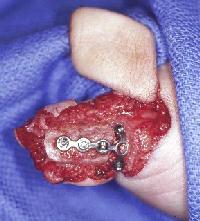

Transferred, ready to cover the bone graft and hardware.